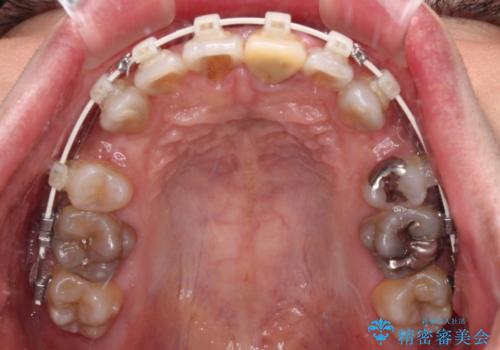

- 審美装置

速やかに治療を進めたいとのことで、表側のワイヤー装置で矯正治療を行うこととしました。

特徴的な歯の色が気になっているとのことで、今後セラミッククラウンによる審美歯科治療を検討されているとのことで、矯正治療の後戻りが落ち着いたタイミングで治療を進めていく予定です。